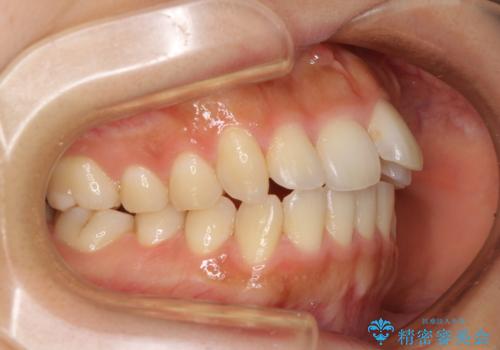

奥歯の咬み合わせを見ると、上顎が下顎に対して相対的に前方にありました。

口元の突出感を改善するためには、上顎臼歯を後方に移動させた咬み合わせにする必要があります。

インビザライン単体で改善することも可能ですが、達成する可能性が高くないため、カリエールディスタライザーという補助装置を併用して、より確実性を上げることとしました。

奥歯の咬み合わせを改善しながら、並行してインビザラインで歯列を整えることとしました。

カリエールディスタライザーを併用したことで、確実かつ短期間で治療を終えることができました。